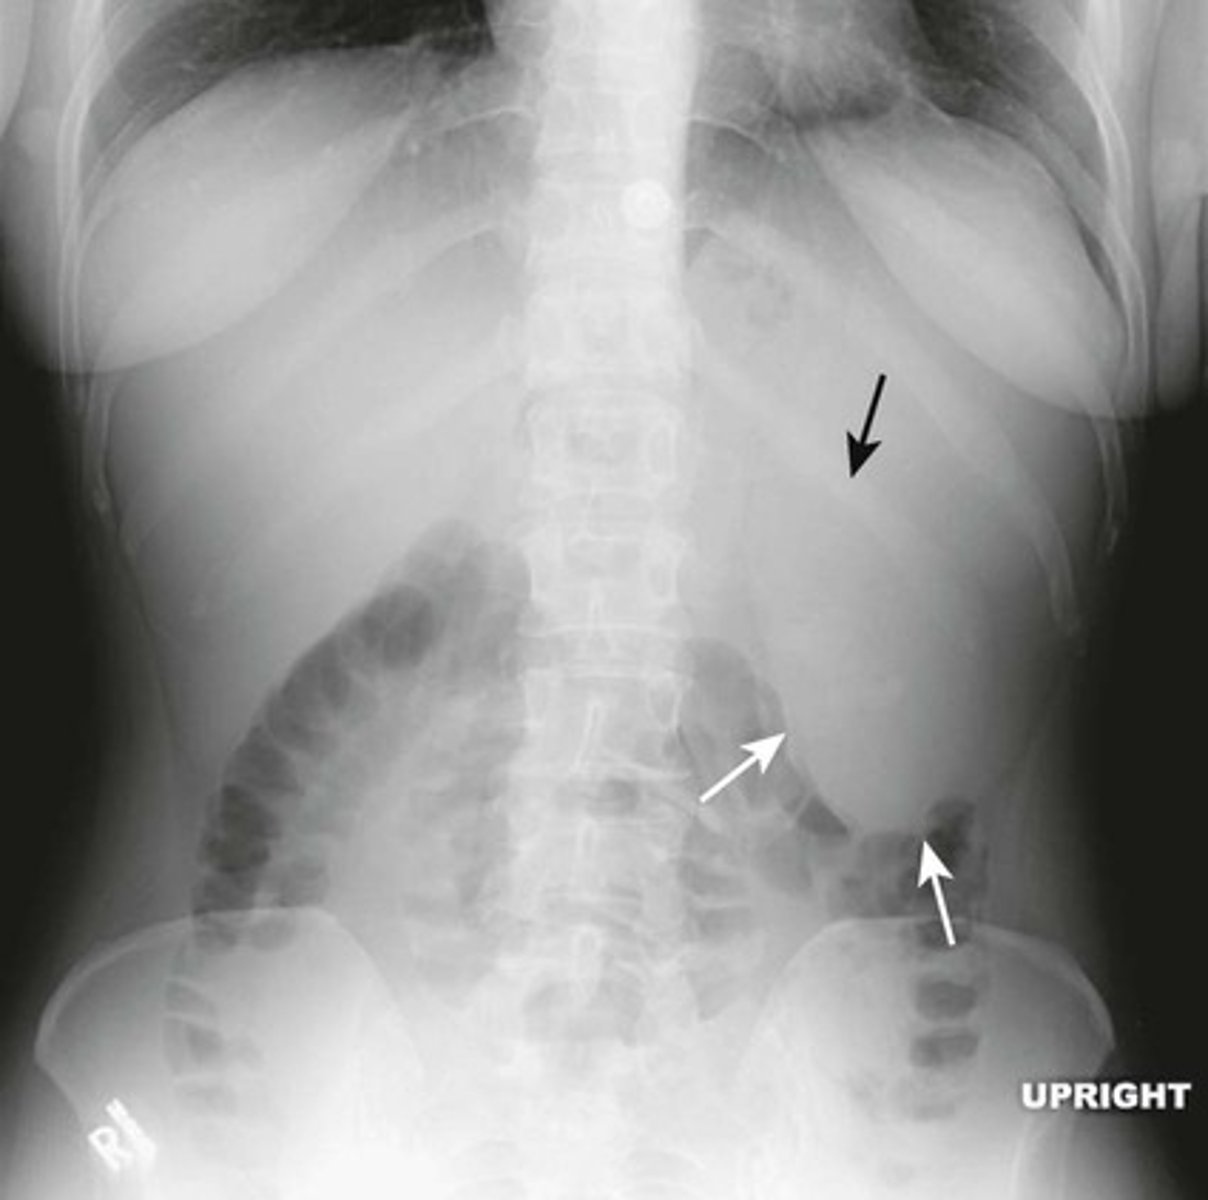

Normal upright abdomen

SOLID BLACK ARROW: normal air-fluid level in stomach

BLACK CIRCLE: short air-filled levels in a few non-dilated loops of small bowel.

DOTTED BLACK ARROW: Free air just below the hemidiaphgram (Usually very few or no air-fluid levels in the colon)

Two things to look for on an upright view of the abdomen are:

1) Air-fluid levels

2) Free intraperitoneal air.